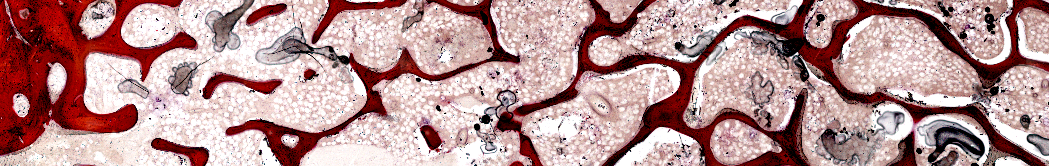

Osseointegration normally relies on ground sections because it’s generally not possible to cut metal implants on a microtome. Surface staining methods are therefore required.

A standard technique in osseointegration is the analysis of new bone formation and bone contact surface within a standard zone around the implant. BIOQUANT includes tools to standardize the thickness of the sampling area around the implant. A zone thickness is specified and then a drawing tool guides a technician in tracing out the sampling area. In the image at the top, a zone thickness of 125 microns was used.